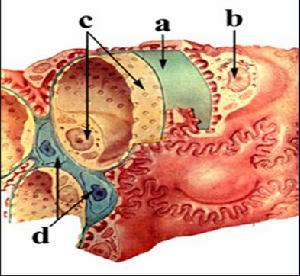

老年人腎病綜合徵老年人腎病綜合徵中繼發性腎病綜合徵發生率高其中以腎澱粉樣變最高約占全部老年患者腎病綜合徵的15%,其次是各種腫瘤,也常引起老年人繼發腎病綜合徵,如胃腸道腫瘤淋巴瘤白血病肺癌發生率為11%還有其他疾病,如老年糖尿病腎病、B型肝炎,某些藥物(非特異性消炎藥、金製劑青黴胺),血管炎、冷球蛋白血症巨球蛋白血症等在原發性腎病綜合徵中病理分型以膜性腎病最為常見。據國外80年代的資料分析:膜性腎病占36.5%,微小病變占19.4%,各類增殖性腎炎占15.3%局灶性腎小球硬化占7.7%,其他類型少見

1.微小病變型 占老年腎病綜合徵25%臨床表現中伴有舒張期高血壓和血肌酐超過正常值,高於成年人而血尿少於成年人,原發性較多

2.膜性腎病 占老年腎病綜合徵70%膜性腎病型常與腫瘤和某些藥物(金製劑青黴胺)有關。腫瘤多與肺腫瘤、胃腸道腫瘤、淋巴瘤白血病有關。臨床症狀無特殊。

3.腎澱粉樣 大部分是原發性澱粉樣變,少數繼發於多發性骨髓瘤和慢性疾病如類風濕關節炎。澱粉樣變可以波及全身時可出現牙齦或直腸的剛果紅染色陽性且預後較差,無有效治療方法。常於診斷後14個月內死亡。